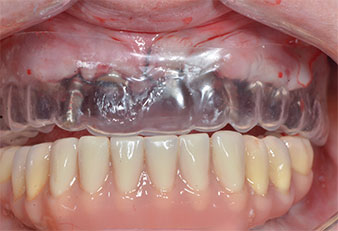

A 41-year-old patient without systemic particularities lost all her teeth due to periodontitis and caries. Finally she had to wear mucosa-supported total dentures in both jaws, with great masticatory difficulties due to the ill-fitting prostheses. The patient decided to have implants placed to support a bar-retained fixed CAD/CAM prosthesis in the mandible.

Three years later it was time for a maxillary denture of the same type. Based on CBCT planning sinus augmentation was avoided with the aid of short implants, and a surgical template was used to transfer the planned positions to the alveolar ridge (Figs. 1 and 2).

Due to the relatively hard bone (D2) in this area, the 10 mm long implant sites at positions 11 and 21 were finalized with a 4 mm diameter rotary drill, in combination with a W&H WS-75 L surgical contra-angle handpiece, the W&H Implantmed implant motor and the optional W&H Osstell ISQ module. In contrast, due to the soft bone the posterior sites were prepared to a final 3 mm diameter using the Piezomed I3P instrument. The implants were finally placed transgingivally to osseointegrate for three months (Figs. 6-10). The existing denture was retained on four provisional implants (Fig. 8).